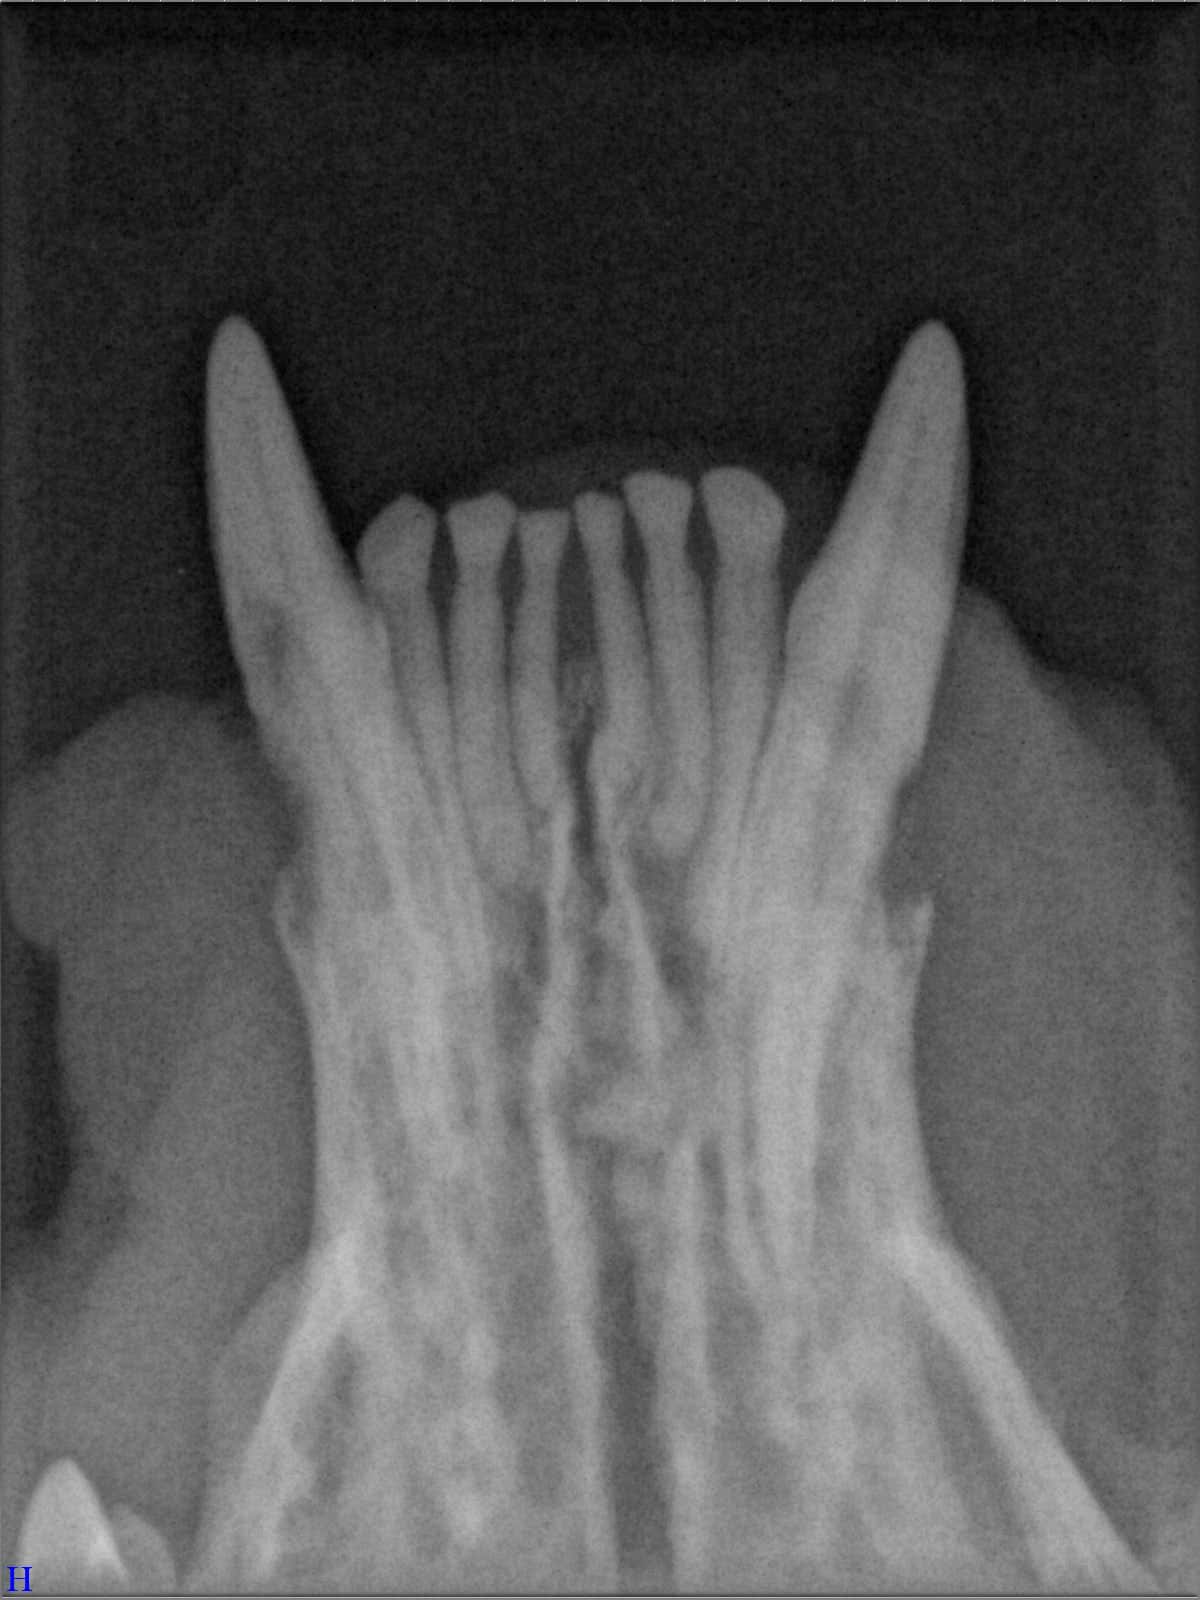

Das sehen Sie von außen – so sieht es auf den Röntgenbildern aus.

FORL Katze Röntgenbild

Röntgenbilder